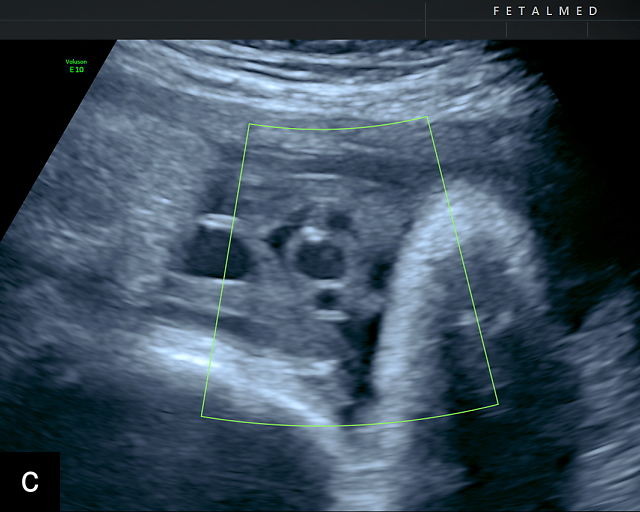

Normal anatomy, development and ultrasound appearance

The umbilical cord serves as the lifeline connecting the fetus to the placenta. It arises from the midportion of the fetal abdomen and typically inserts into the center of the placenta (Figure 16). The average length of the umbilical cord is approximately 55 cm (22 inches).185 It contains three vessels: two arteries, which originate from the fetal left and right internal iliac arteries, and one vein, collectively referred to as a three-vessel cord.

Normal appearance of the umbilical cord with two umbilical arteries and a single vein. (a–c) Cross-section of the umbilical cord on grayscale (a,b) and power Doppler (c) ultrasound. In the normal cord, three vessels are visible: a larger umbilical vein and two smaller umbilical arteries. This characteristic appearance is often referred to as the 'Mickey Mouse' sign, the larger circle (umbilical vein) representing Mickey’s face while the smaller circles (arteries) form his ears. (d–g) Grayscale (d) and color Doppler (e–g) images of transverse section of the lower fetal abdomen showing the two umbilical arteries diverging around the fetal bladder. (h) Longitudinal ultrasound view with color Doppler of a normal umbilical cord showing three vessels present in each coil: two arteries with flow in one direction and a single vein with flow in the opposite direction.

The umbilical vein carries oxygenated blood from the placenta to the fetus, while the two umbilical arteries return deoxygenated blood and waste products from the fetus to the placenta for exchange with the maternal circulation. These vessels are surrounded and protected by Wharton’s jelly, a specialized connective tissue derived from the extraembryonic mesoblast, which cushions the vessels and prevents compression. As the umbilical cord approaches its placental insertion, the two arteries form Hyrtl’s anastomosis, a connection that helps equalize blood flow between the arteries.

At a minimum, the mid-trimester ultrasound should include identification and documentation of the umbilical cord's fetal and placental insertions, as well as the number of cord vessels.66,186,187 In a transverse grayscale section of the cord, the two umbilical arteries can be visualized alongside the larger, thinner-walled umbilical vein, creating a characteristic ‘Mickey Mouse’ appearance (Figure 16a–c). Additionally, in a transverse section of the lower fetal abdomen, the umbilical arteries are seen encircling the fetal bladder. This can be seen on grayscale ultrasound and confirmed with color flow Doppler (Figure 16d–g).

A normal umbilical cord is helical, with an average of 2.1 coils per 10 cm of cord length.188,189 The majority of umbilical cords exhibit a leftward (counterclockwise) twist, with a left-to-right twist ratio of approximately 7 : 1, making the rightward (clockwise) twist significantly less common.185,190,191 This twisting structure is believed to provide additional protection against compression and kinking during pregnancy.192